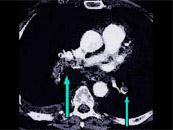

问题 该病人突发胸部疼痛,进行性呼吸困难,行X线片检查,提示右下肺病变,急诊CT平扫加增强,如图所示,则 ( )

选项 A.X线片示右下肺实变影 B.SCT增强扫描示右侧肺动脉主干完全性充盈缺损 C.右肺动脉开口处见不规则软组织密度影 D.考虑为右侧肺动脉(中央性)栓塞 E.考虑为右侧肺癌

答案 ABCD